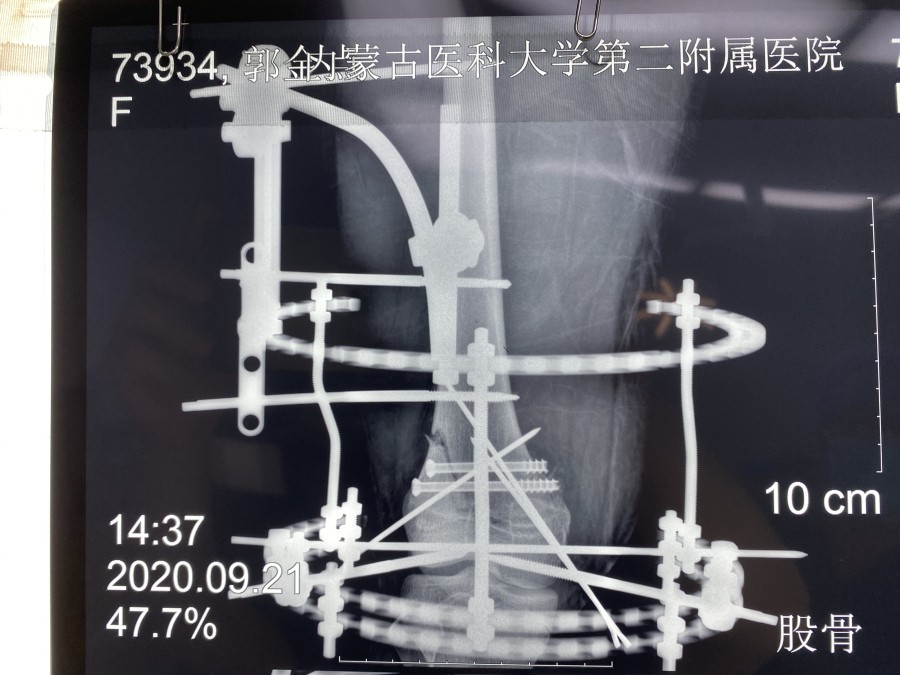

幸运的是MRI检查没有膝关节韧带和半月板的损伤。考虑到小郭的职业生涯,不能出现医源性肌肉等软组织损伤、以及运动员发达的大腿肌肉和术后快速康复的需求等等,小儿骨科团队进行了认真的术前讨论,9月21日,由韦宜山主任主刀实施了闭合复位经皮空心螺钉联合克氏针辅助Ilizarov环形外固定架手术治疗。手术非常成功,骨折端完全解剖复位,术后第1天小郭即开始床上膝关节主动和被动活动,第3天已可下地进行短时间不负重训炼,术后第10天已经可以独立扶双拐行走,10月9日,小郭顺利康复出院。术后,小郭一日三餐由我院营养部免费提供营养餐,病区护理人员专人负责陪护。